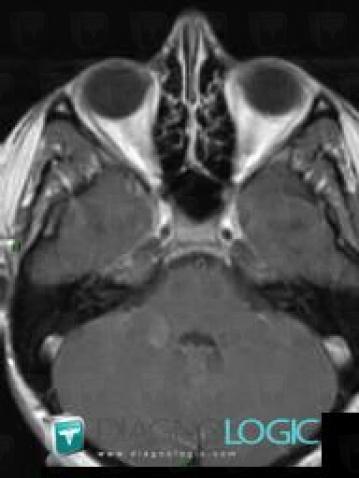

Multiple sclerosis, Posterior fossa, MRI

Here is the specific information in the key image above:

- Diagnosis Multiple sclerosis, Location(s) Posterior fossa, with gamuts Multifocal infratentorial lesions, Infratentorial T2W or FLAIR hyperintense lesion